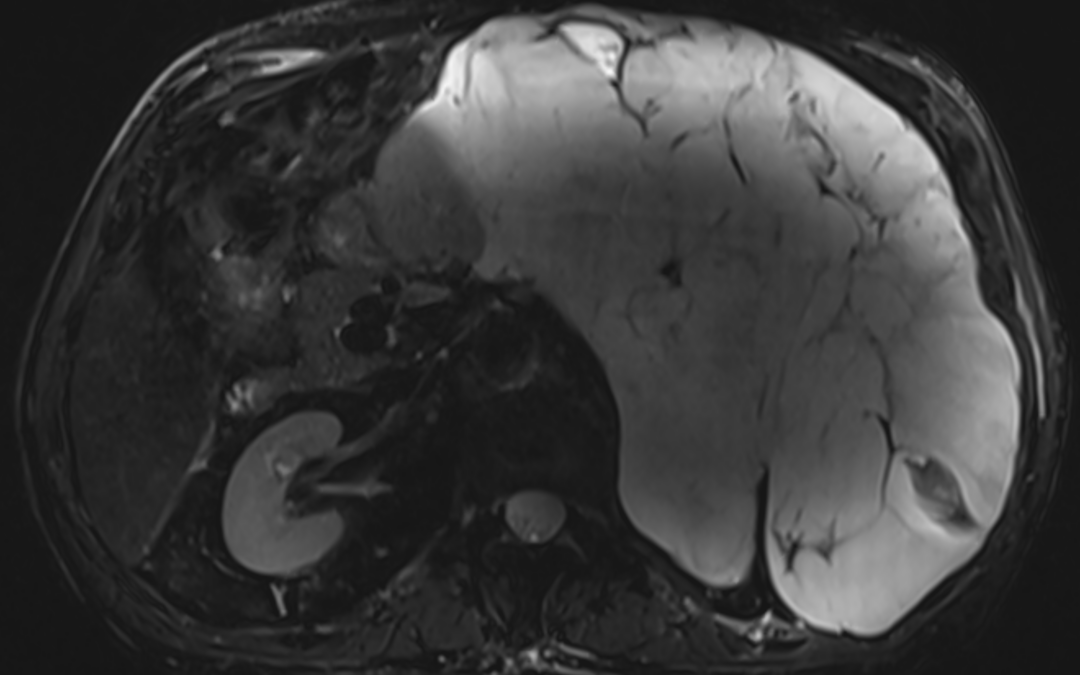

Varón de 80 que consulta por dolor en hipocondrio izquierdo de dos meses de evolución y sensación de masa. El dolor aumenta ligeramente con la inspiración profunda.Comenta pérdida de peso hace 5 años que no ha progresado.Exploración Física: Abdomen blando y...